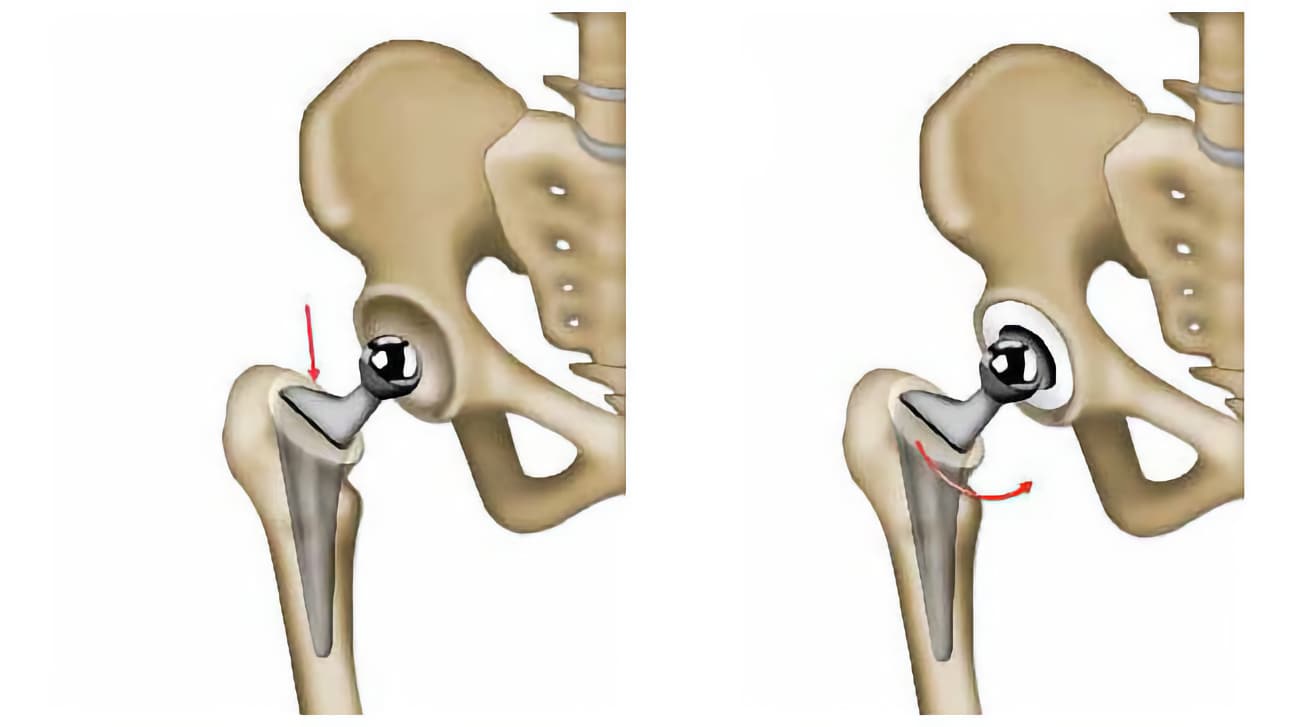

Το οστό πρέπει να προσαρμόζει απόλυτα στα μέρη της πρόθεσης. Για το λόγο αυτό, ο χειρουργός δοκιμάζει διάφορες προθέσεις. Διασφαλίζει τη συγκράτησή τους στο οστό, την κατεύθυνσή τους, μείωνει στο ελάχιστο τον κίνδυνο εξάρθρωσης, κτλ.

Εάν αντικατασταθεί μόνο η κεφαλή του μηριαίου, η πρόθεση αποτελείται από ένα στέλεχος, το οποίο εισάγεται στο μηριαίο. Στο στέλεχος εφαρμόζει ένα τμήμα με σφαιρικό σχήμα (κεφαλή πρόθεσης). Στην ιατρική γλώσσα, μιλάμε για πρόθεση μηριαίας κεφαλής.

Όταν πρέπει να αντικατασταθούν όλα τα μέρη της άρθρωσης (ολική πρόθεση), ο χειρουργός προσθέτει ένα τμήμα σε σχήμα κούπας (το κυπέλλιο), που στερεώνεται στην κοτύλη.

Στη συνέχεια, ο χειρουργός ενώνει τα δύο μέρη της πρόθεσης και διασφαλίζει τη σταθερή συγκράτησή τους σε όλες τις θέσεις. Τέλος, τοποθετεί στη θέση τους όλα τα στοιχεία που περιβάλλουν την άρθρωση (θύλακος, μύες, κτλ.).

Ο χειρουργός σας μπορεί να προβεί σε επιπλέον ενέργειες για τη βελτίωση της λειτουργίας της πρόθεσης και την ελαχιστοποίηση του κινδύνου εξάρθρωσης (εξάρθρημα).

Μερικές φορές, δημιουργείται στην άρθρωση νέο οστό (οστεοποιήσεις), γεγονός που περιορίζει τις κινήσεις του ισχίου. Κυρίως τους πρώτους μήνες, τα δύο μέρη της πρόθεσης μπορεί να υποστούν εξάρθρωση (εξάρθρημα). Για το λόγο αυτό, ο ασθενής μαθαίνει να αποφεύγει συγκεκριμένες κινήσεις.